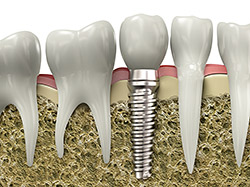

If you have missing teeth, it is crucial to replace them. Without all your teeth, chewing and eating can destabilize your bite and cause you discomfort. When teeth are missing, your mouth can shift and even cause your face to look older. Implants are a great way to replace your missing teeth, and if properly maintained, can last a lifetime!

An implant is a new tooth made of metal and porcelain that looks just like your natural tooth. It’s composed of two main parts: One part is the titanium implant body that takes the place of the missing root, and the second part is the tooth-colored crown that is cemented on top of the implant. With implant treatment, you can smile confidently knowing no one will ever suspect you have a replacement tooth.

In addition to tooth replacement, implants may be used to anchor dentures, especially lower dentures that tend to shift when you talk or chew. For patients with removable partial dentures, implants can replace missing teeth so you have a more natural-looking smile.